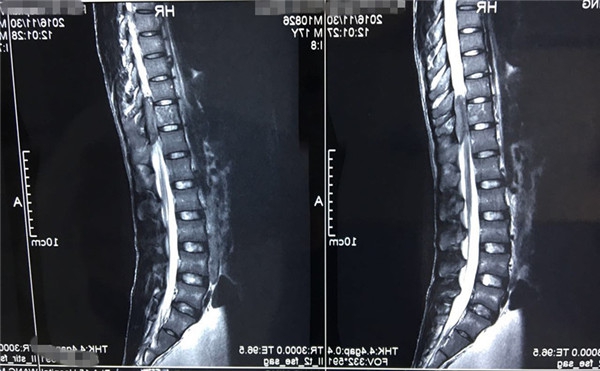

术前MRI